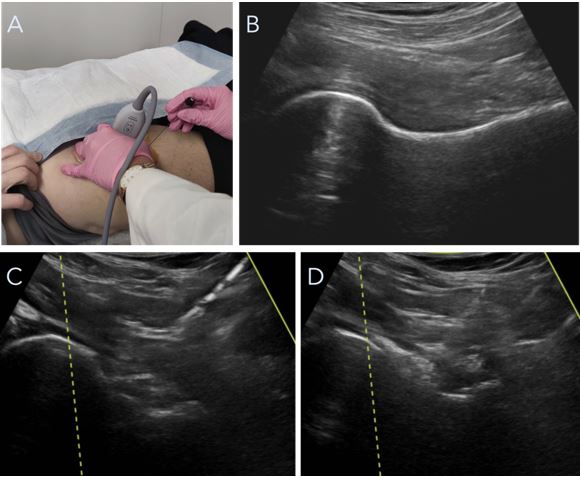

La infiltración de corticosteroides o de sustancias biológicas intraarticulares es un procedimiento relativamente común en el tratamiento del PFA. Los tratamientos biológicos pueden ser autólogos o derivados sintéticos, por ejemplo, el ácido hialurónico. La infiltración de anestésico local de manera aislada se utiliza para el diagnóstico de patología articular de cadera (en este caso PFA) especialmente en los casos en los que el paciente no refiere una clínica clara o se superponen otras patologías, como dolor lumbar o trocantéreo que dificultan el diagnóstico. El resto de las infiltraciones se aplican para el tratamiento del dolor, generalmente junto con el tratamiento fisioterápico en pacientes en los que se opta de forma inicial por manejo conservador (Fig. 6)5. Dichos pacientes son aquellos que presentan clínica leve/moderada de dolor con las maniobras exploratorias sin gran impedimento para la actividad diaria normal, o bien, pacientes no candidatos a cirugía artroscópica por degeneración articular avanzada como hablaremos más adelante. Actualmente no existe un consenso estandarizado en cuanto a la elección de los diferentes tipos de infiltraciones, puesto que la evidencia científica existente para el tratamiento conservador del PFA es muy variada en resultado. En nuestra práctica clínica habitual, preferimos iniciar el tratamiento con una infiltración de corticosteroide y anestésico local (utilizamos 2.0 ml o 40 mg de acetato de metilprednisolona, 2.0 ml al 1 % de lidocaína y 1.0 ml al 0.5 % de bupivacaína) además del tratamiento fisioterápico personalizado para cada paciente y la correspondiente modificación de la actividad. En caso de que el dolor regrese y el paciente quiera continuar con dicho tratamiento, no recomendamos más corticoesteroides. En su lugar, se opta por continuar con inyecciones de plasma rico en plaquetas (PRP, sistema de Arthrex®) y/o ácido hialurónico (empleamos más frecuentemente TriVisc®, Triluron®, Gelsyn®, Monovisc® u Orthovisc®). Nuestra recomendación es administrar una serie de tres inyecciones, una por semana. Las infiltraciones se realizan en consulta, guiadas mediante la utilización de una sonda ecográfica. Este tratamiento se podría repetir cada seis meses.

Figura 6. A) Infiltración de cadera ecoguiada. B) Imagen ecográfica de cabeza y cuello femoral. C) Aguja en dirección a cuello femoral proximal. D) Imagen hiperecogénica en cuello y cabeza femoral que indica localización de infiltración.